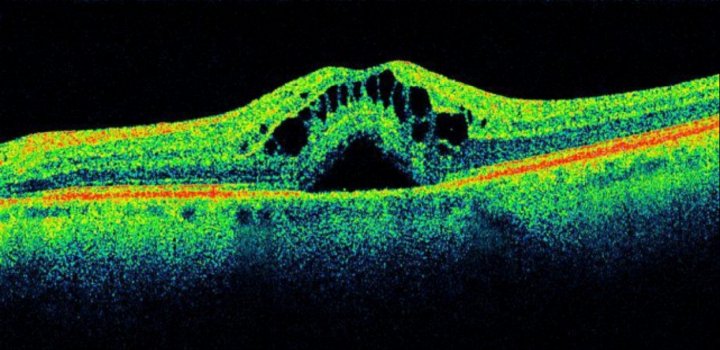

Диагностика зрения: Когерентная томография сетчатки